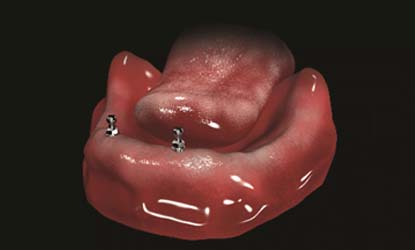

Problema: Trūksta visų dantų

Tikslas:

Pakeisti trūkstamus dantis išimamais protezais (ekonomiškiausias gydymo būdas)

Rezultatas:

Atkurta kramtymo ir estetinė funkcija išimamais dantų protezais